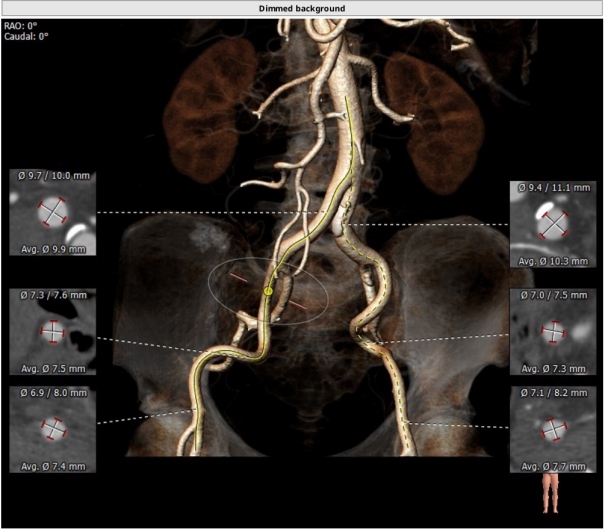

TYPE1型二叶瓣,重度钙化,左右可见钙化融合脊,法式窦结构可,双冠高度可,升主动脉增宽,最宽处约46 mm,心脏角度不大,左室大,心尖部可见囊状造影剂填充,考虑多系小室壁瘤,术中需谨慎操作,主动脉弓部走行较平缓。

瓣环平均直径:21.9 mm,左室流出道平均直径:21.6 mm,钙化积分:865.9 mm³